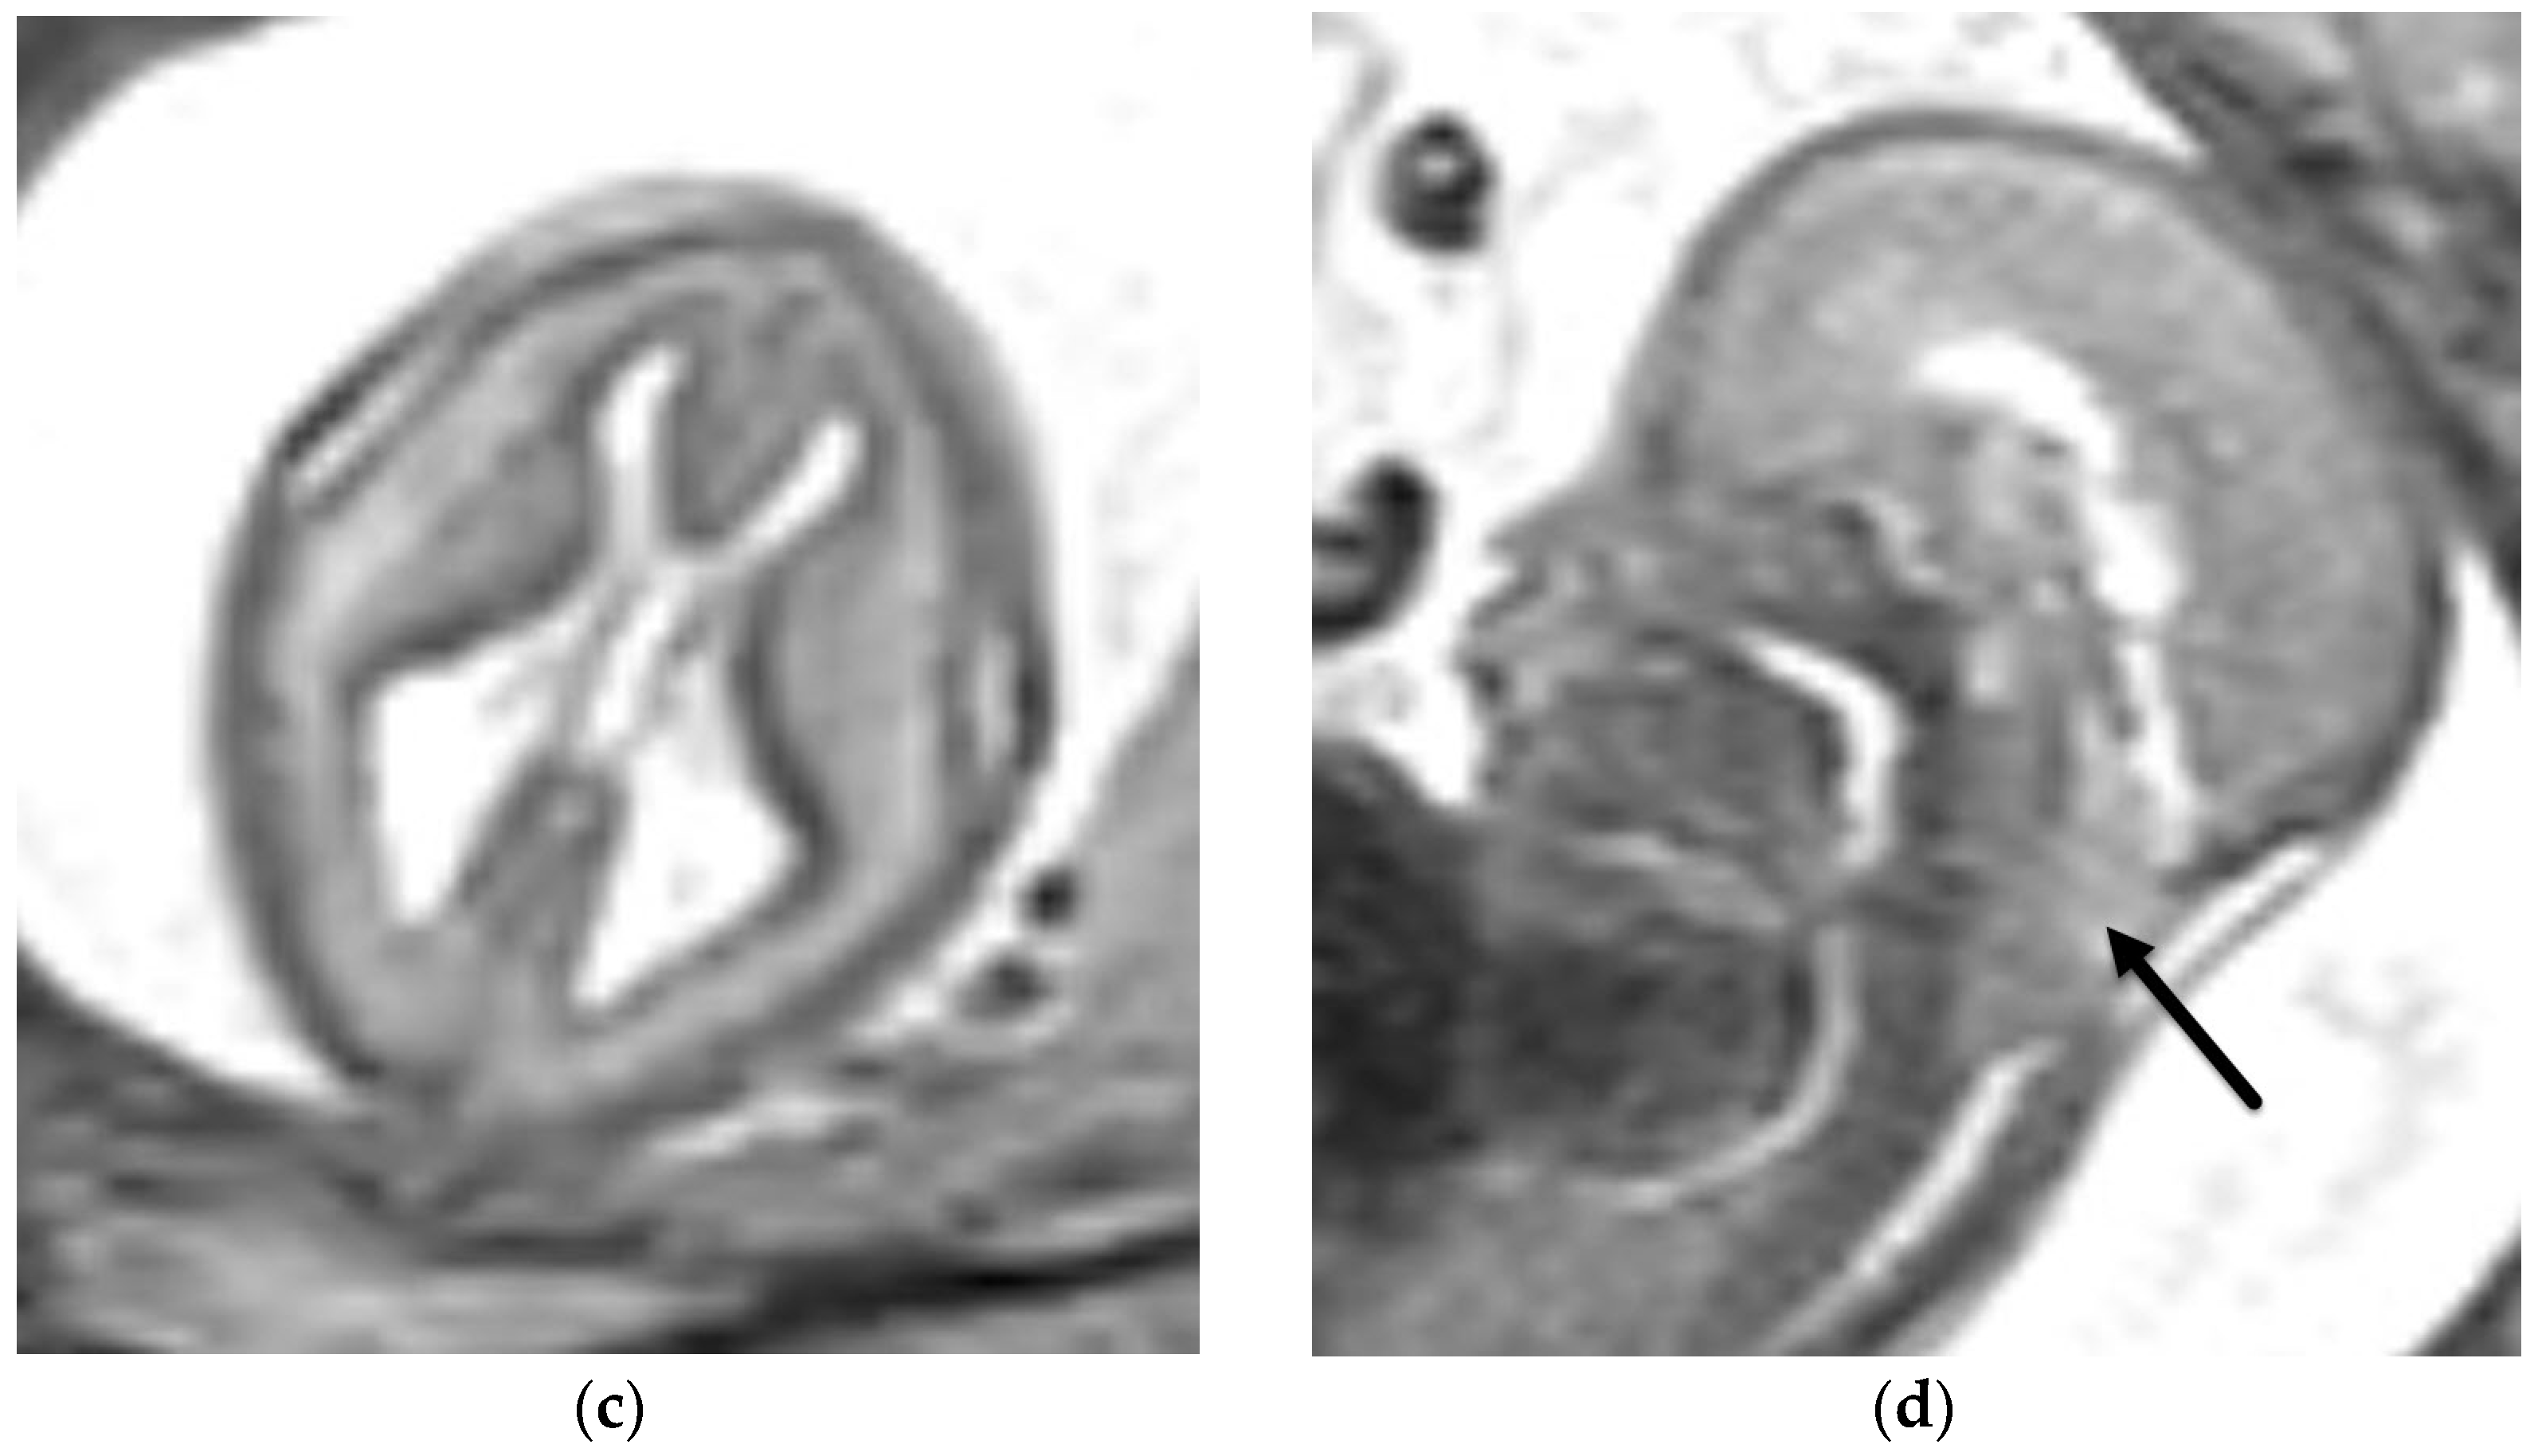

3.1.1. Aqueductal Stenosis

- Heaphy-Henault, K.; Guimaraes, C.; Mehollin-Ray, A.; Cassady, C.I.; Zhang, W.; Desai, N.K.; Paldino, M.J. Congenital aqueductal stenosis: Findings at fetal MRI that accurately predict a postnatal diagnosis. Am. J. Neuroradiol. 2018, 39, 942–948. [Google Scholar] [CrossRef] [PubMed] [Green Version]

- Kline-Fath, B.M.; Arroyo, M.S.; Calvo-Garcia, M.A.; Horn, P.S.; Thomas, C. Prenatal aqueduct stenosis: Association with rhombencephalosynapsis and neonatal outcome. Prenat. Diagn. 2018, 38, 1028–1034. [Google Scholar] [CrossRef] [PubMed]